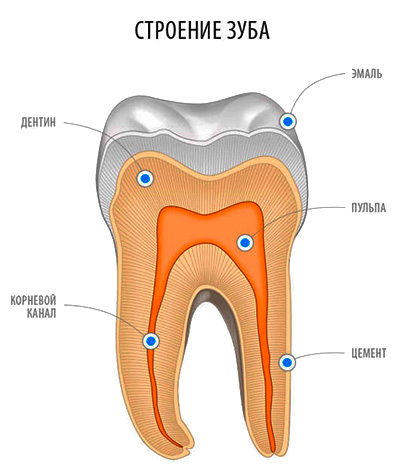

«Fogszuvasodás» - a latin neve utal, hogy a folyamat a pusztulás. És a „dentin” származik a latin „fogász”, ami azt jelenti, „fog”. Lényegében a dentin a fog az alapon és a zománc.

Dentin különbözik jelentősen a kémiai összetétele és szerkezete a fogzománc. Ez sokkal kevésbé robusztus és 20% áll szerves vegyületek. A vastagság a dentin a fog eléri átlagosan 2-6 mm-es. Így dentin szinte a teljes vastagságban áthatja dentintubulus, melyek az idegvégződéseket.